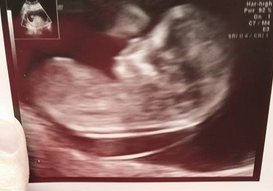

AW: NT scan went great! PIP

NT scan went FABULOUS. They said it would take an hour and baby was so co-operative they were done in about 8 minutes. Everything was perfect. He was putting his hands in his mouth, and at the very end flipped upside down. so cute!